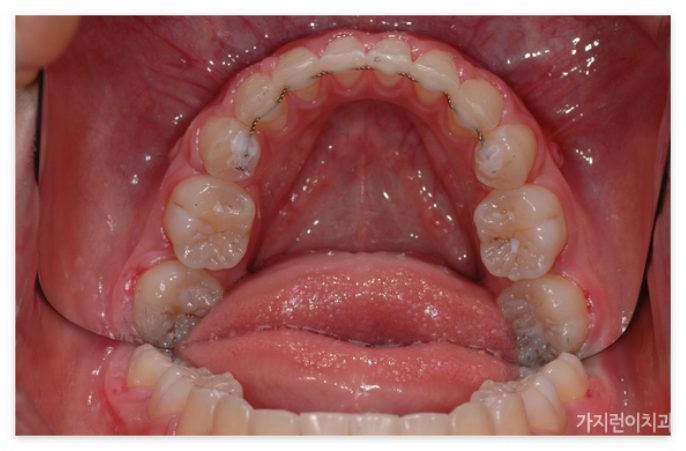

이 케이스는 1년 8개월의 치료기간이 소요된 환자분의 전후차이입니다. 많은 분들이 교정 후에 다시 원상태로 돌아가거나 더 심한 케이스로 변질되는 것은 아닐까 고민하시는데요. 해당 환자분은 교정 전후 차이와 7년 후의 모습까지 확인이 된 상태입니다. 환자분의 경우 잇몸뼈 돌출과 치아 돌출도 어느 정도 있는 경우여서 잇몸이 과도하게 보이는 스타일이었는데요.

앞으로 돌출된 치아를 구조적으로 안쪽으로 집어넣기 위해서는 공간의 확보가 필요합니다. 그래서 많은 분들이 발치를 진행하는데요. 위와 같은 경우도 상하악 제1소구치를 발치한 후에 충분한 공간을 확보한 후에 진행을 하였습니다. 특히 발치가 무조건 안 좋고 비발치가 좋은 것이라고 오해하는 경우가 있는데 발치할 케이스임에도 비발치로 진행하게 되면 오히려 더 안 좋은 결과를 안아볼 수 있기 때문에 상악 전치의 후방이동을 위한 충분한 공간확보를 위한 과정이라고 이해하면 되겠습니다. 본원에서는 서울 거미스마일 교정을 위해 미니스크류를 식립해 상악 전치를 위로 올리는 힘을 추가 했습니다. 미니스크류를 이용하면 개선할 충분한 힘이 가해지기 때문에 상하악 전치가 동시에 이동할 수 있습니다.